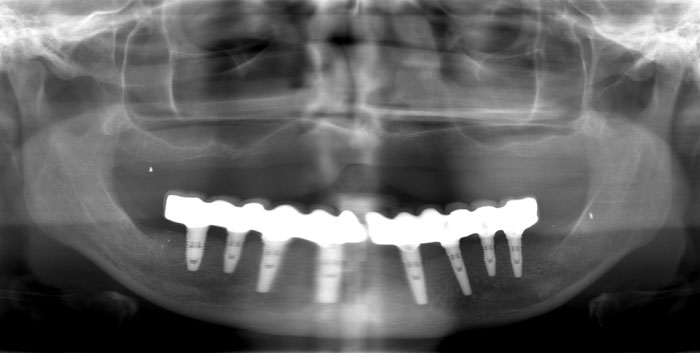

Durch ein genetisches Leiden wurde das Gebiss des Patienten zerstört. Die drei Röntgenbilder zeigen das Voranschreiten der Krankheit. Brücke auf acht NOBEL BIOCARE-Zahnimplantaten und herausnehmbarer Zahnersatz am Oberkiefer.